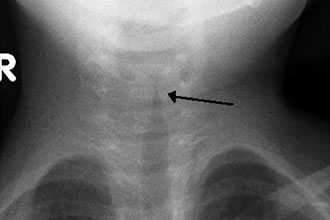

Первым признаком является появление царапания в горле, шумного дыхания, слышного на расстоянии. Отмечается одышка с затрудненным вдохом.

Появляется резкая бледность кожи, особенно в районе носогубного треугольника. В зависимости от стадии ларингоспазма, могут присутствовать симптомы, свидетельствующие о вовлечении в процесс дыхания вспомогательной мускулатуры, западение надключичных впадин, подложечной области и межреберных промежутков.

Пациент может потерять сознание. Вся симптоматика обусловлена выраженным отеком гортани, в результате чего дыхательная щель оказывается резко суженной, а организм начинает испытывать недостаток в кислороде. При развитии острой дыхательной недостаточности необходимо срочное проведение неотложных мероприятий. В противном случае развивающийся отек гортани способствует развитию удушья и асфиксии.

Уточнить аллергический ларингит, его характер поражения и локализацию возможно посредством ларингоскопии. Для такой природы поражения характерна бледность слизистых оболочек, в отличие от ее гиперемии при воспалительных процессах, обусловленных инфекционными агентами. При этом может отмечаться выраженный отек гортани.